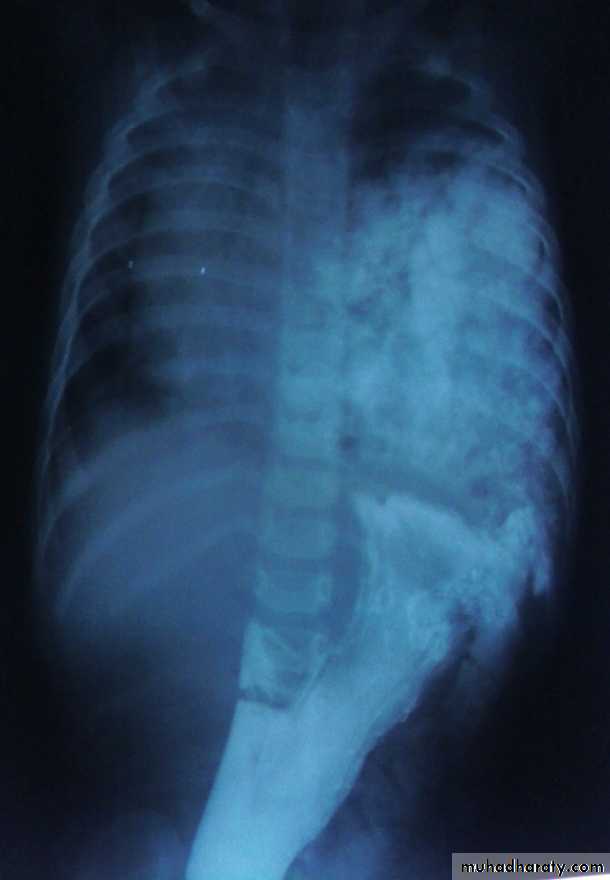

Nephroblastoma (Wilms' tumor).

Clinical presentation :-

80% asymptomatic flank mass.Hematuria.

Fever.

Hypertension.

TREATMENT

MDTCHEMOTHERAPY

SURGERY